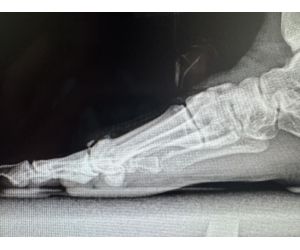

Ankle Arthroscopy and

MIFAS

In some situations, direct repair of the lateral ankle ligaments is not feasible. In these cases, ligamentoplasty becomes necessary, with a clear...